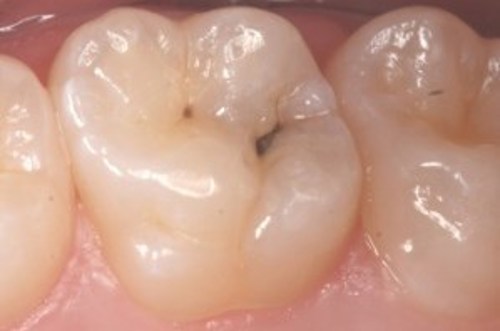

Hullet bliver lavet

Billederne nedenfor viser, hvordan hullet bliver lavet.

På første billede ses hullet som en sort plet på tanden.

På andet billede er tandoverfladen boret væk, så man kan se ned i hullet.

På sidste billede er hullet renset og der er lagt en plastfyldning i.